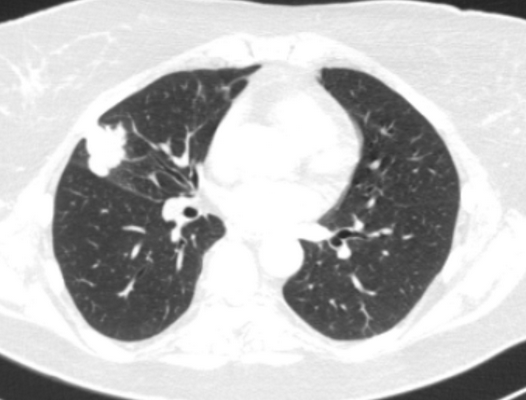

Фото 3 — Лобэктомия

Фото 4 — Пневмонэктомия

Фото 5 — Схема верхней бронхопластической лобэктомии